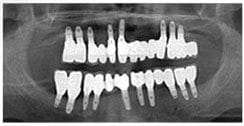

X 光片

術前X光片

術後X光片